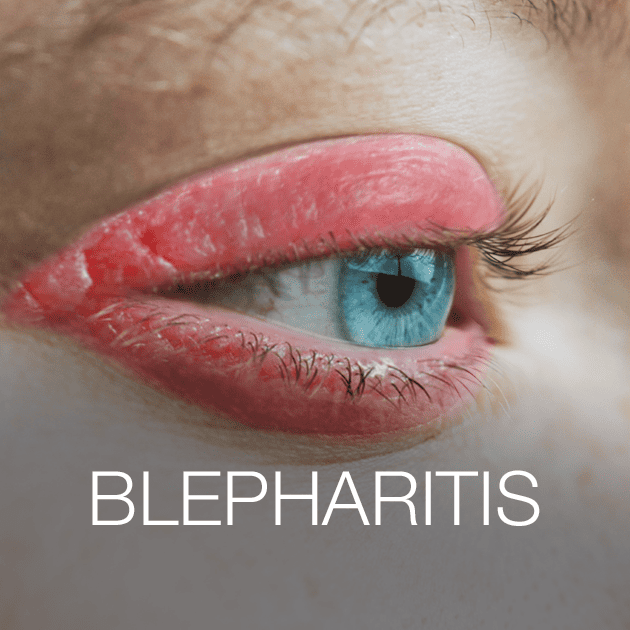

Demodex mites are usually harmless and do not cause any symptoms. However, in some people, infestations of Demodex mites can lead to a variety of problems, including dry eye, eye irritation, and inflammation of the eyelids. Demodex mites are more common in people with certain risk factors, such as advanced age, a history of eye surgery, and certain medical conditions, such as rosacea (a skin condition that affects the face).

Demodex mites are usually harmless and do not cause any symptoms. However, in some people, infestations of Demodex mites can lead to a variety of problems, including dry eye, eye irritation, and inflammation of the eyelids. Demodex mites are more common in people with certain risk factors, such as advanced age, a history of eye surgery, and certain medical conditions, such as rosacea (a skin condition that affects the face).